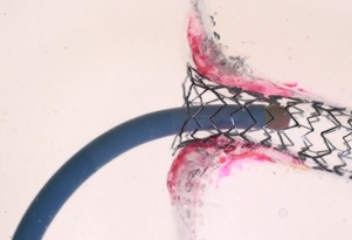

TRUE 360° FLARED APPOSITION

Novel 2-in-1 dual balloon design allows for inflation of a non-compliant distal balloon to anchor the system, while inflation of the compliant, low-pressure proximal balloon conforms the stent to the wall of the ostium.